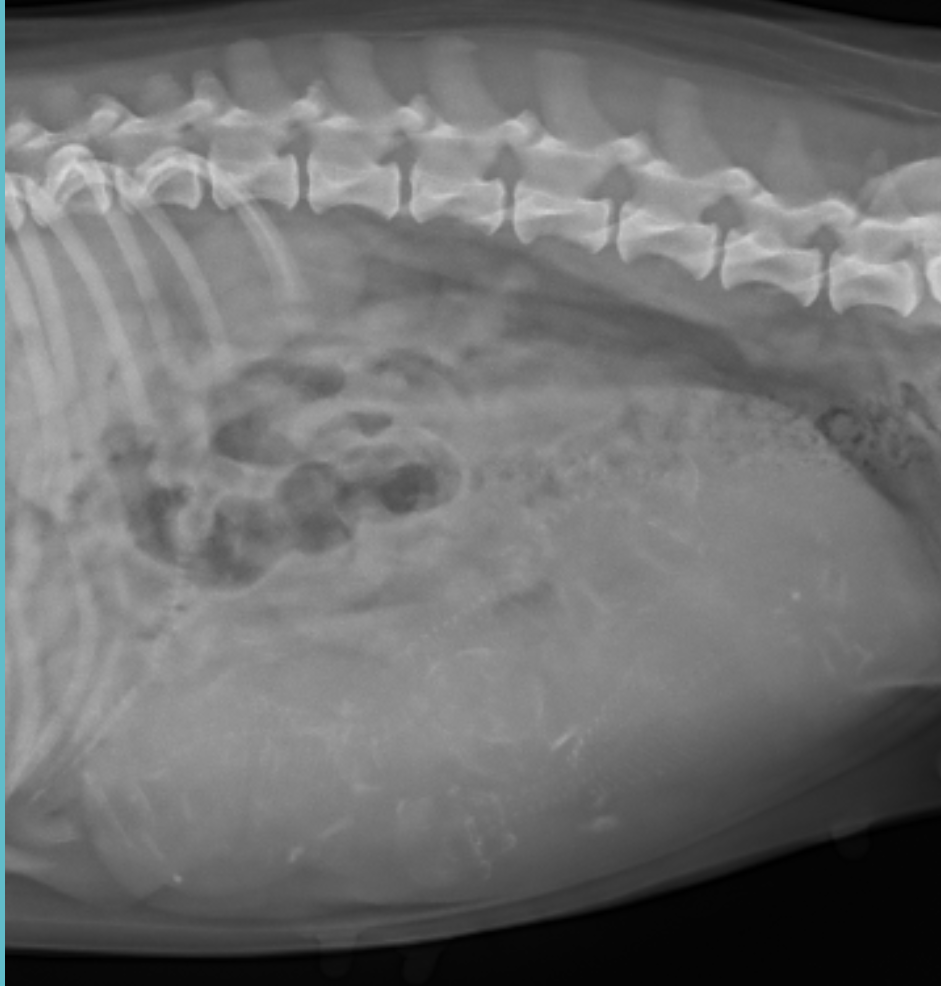

Although there’s still some time left before they make their grand arrival into the world, they are now faintly visible on radiography. This is an important appointment for a pregnant dog to have. If a dam is pregnant with only one puppy, the chances of her going into labor spontaneously are very low. Even if they do, their pup would likely be too large to deliver naturally anyway. Most singleton litters require a cesarean delivery.

Fortunately, that’s not the case with Skye. Her imaging looked great. Her puppies’ skeletons are still calcifying so you’ll have to squint a bit, but see if you can spot them all.

Yes, this is a trick question.

How many did you count? Did you see any at all? Let me help you out here a bit:

This is also a trick question.

As a nurse practitioner, I’m no stranger to reading x-rays. Skye’s veterinarian counted four puppies, until I squinted a bit and pointed something out to her.

If you look at the puppy outlined in green, there’s actually another spinal column that crosses behind it. It’s very faint due to the fact that it’s on the other side of her abdomen, but it’s undeniably there. So, I suspect that she’s expecting a total of five little bundles of joy. Hooray!